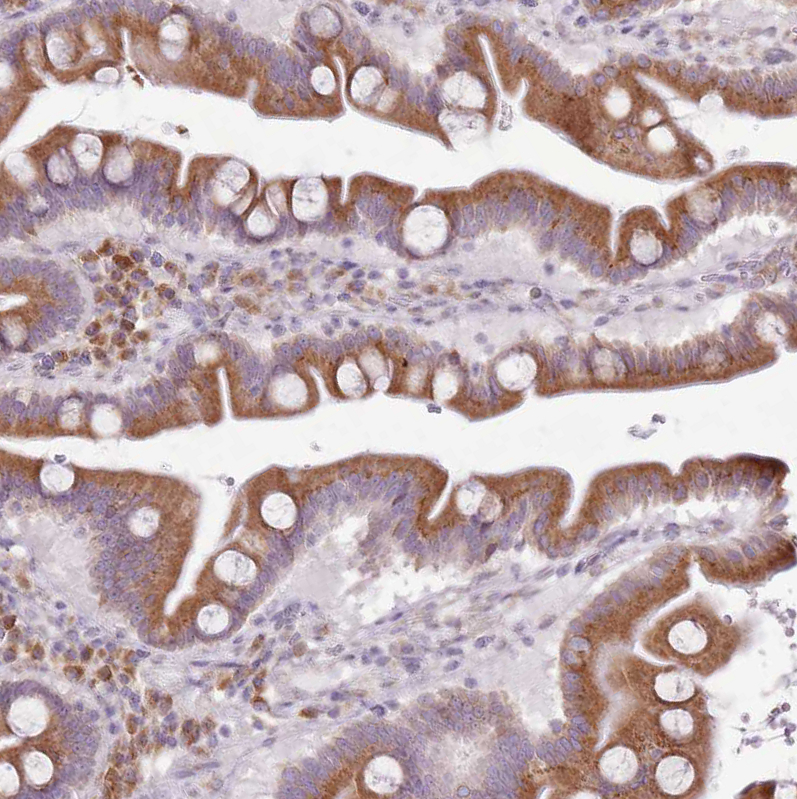

Immunohistochemistry analysis in human endometrium and skeletal muscle tissues using HPA047139 antibody. Corresponding TMED10 RNA-seq data are presented for the same tissues.